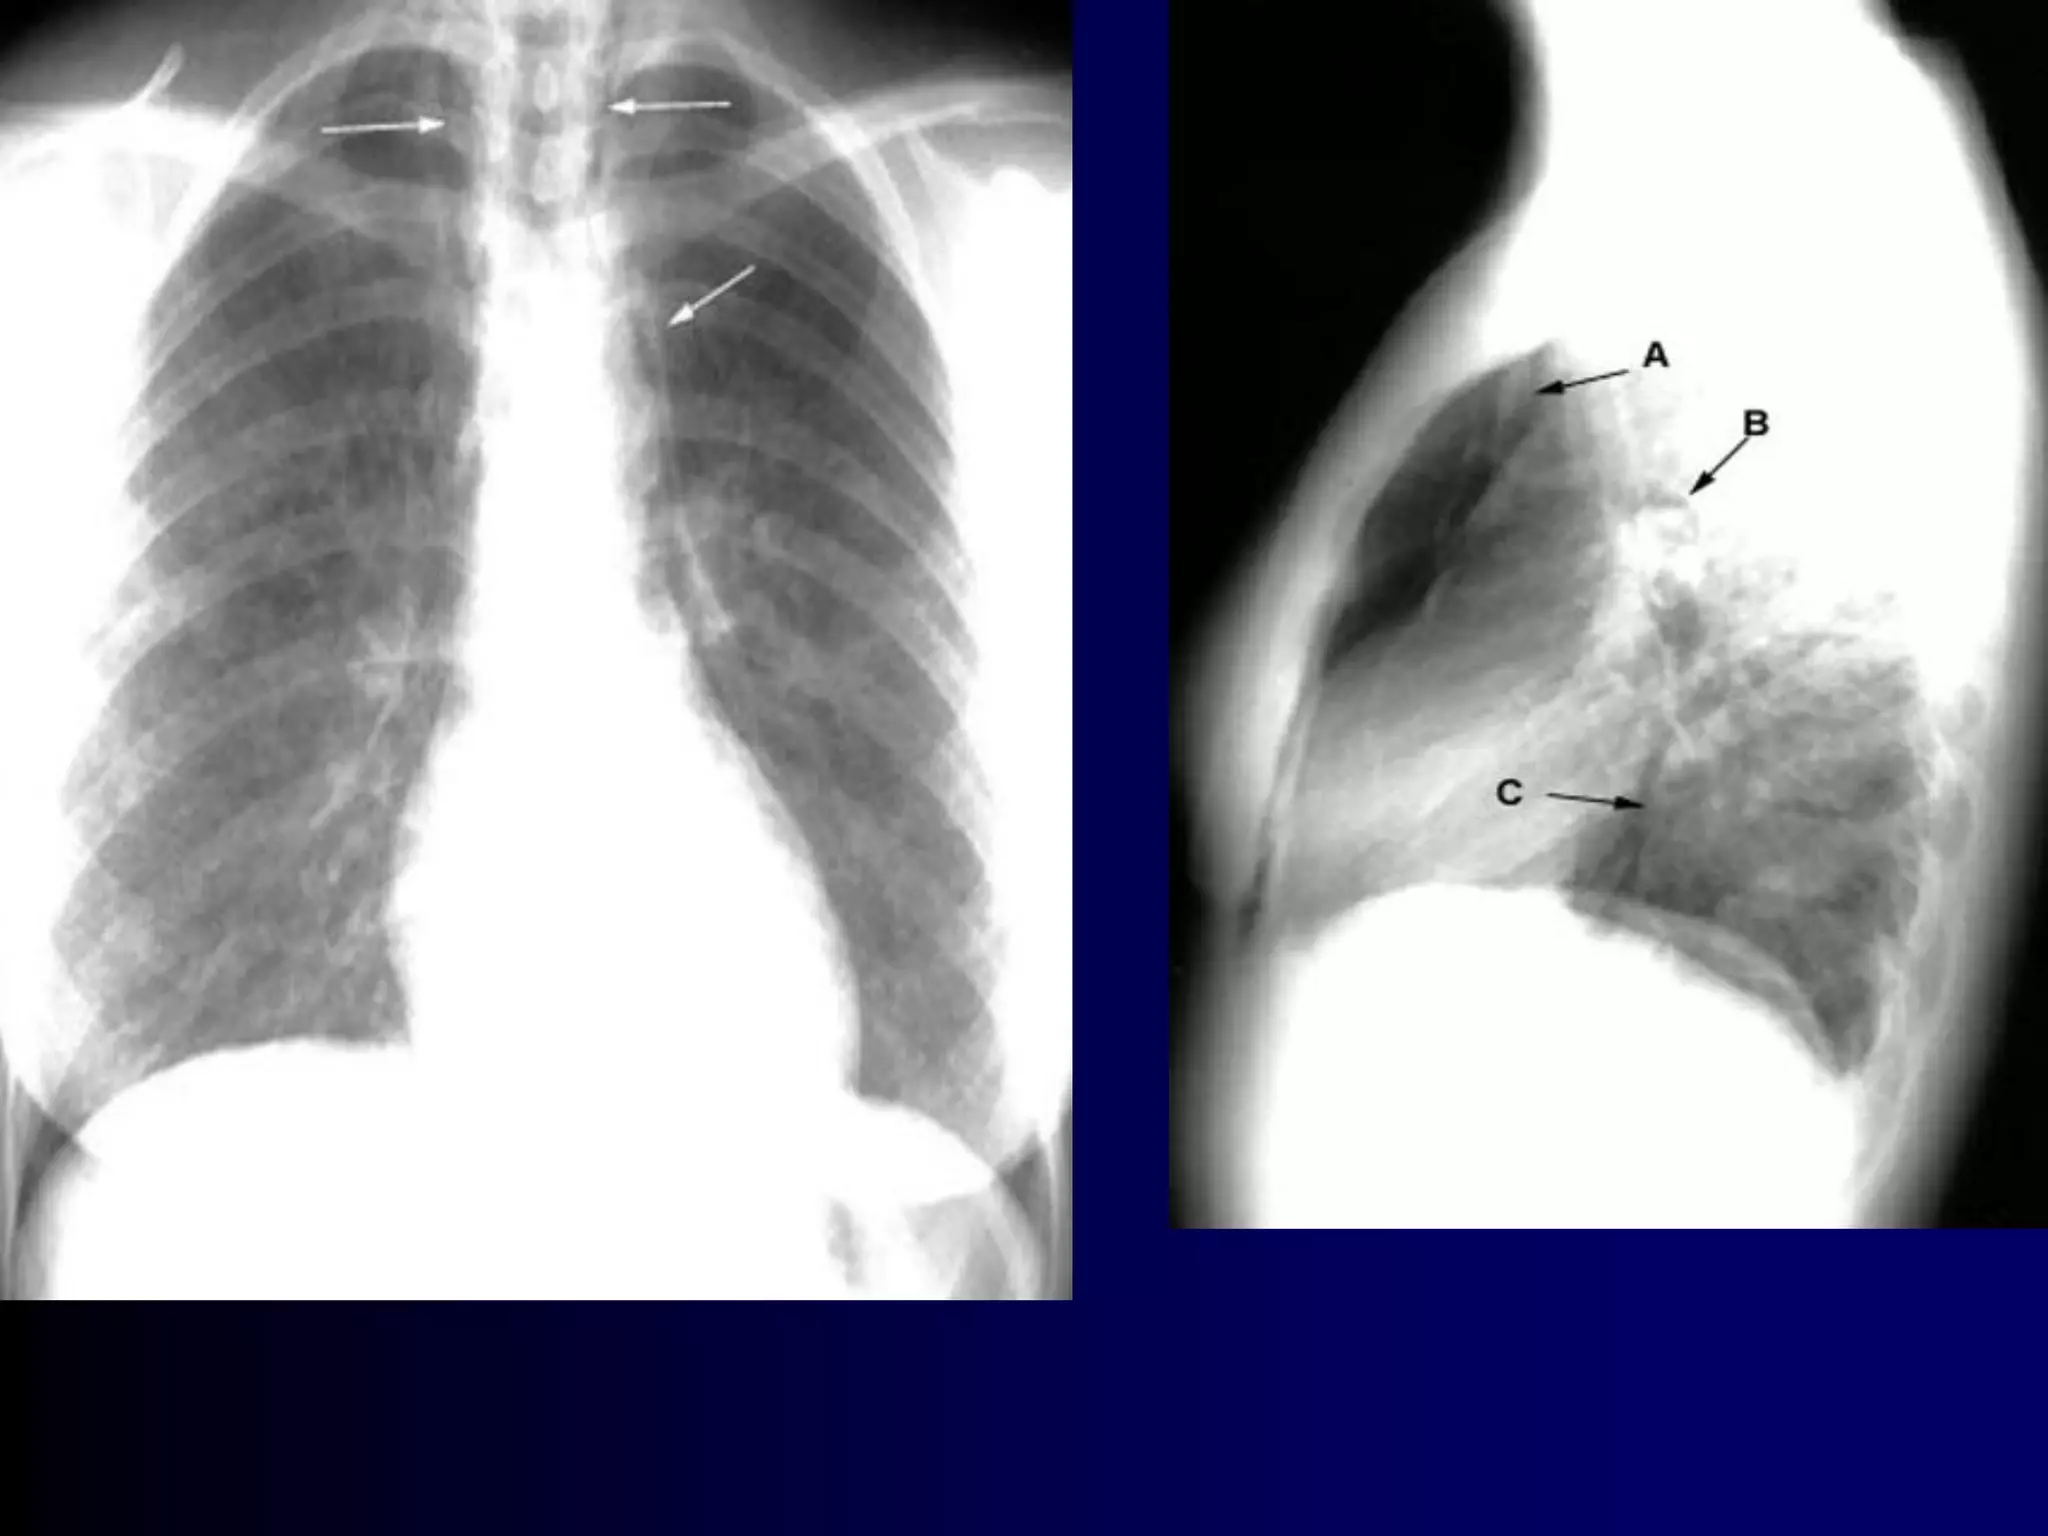

Allergic bronchopulmonary aspergillosis (ABPA) is an

ongoing hypersensitivity reaction in response to

bronchial colonization by Aspergillus, and is a common

cause of poorly controlled asthma. Cystic fibrosis

patients are also often affected. Bronchial obstruction

by mucus and chronic inflammation can lead to

bronchiectasis and lung fibrosis with irreversible loss

of lung function.

Clinical features: Cough productive of sputum, frequent

"bronchitis"; often with dyspnea and wheezing.

Diagnosis:

By constellation of symptoms and objective

findings. "Classic" ABPA would include the

following:

Asthma history

Immediate reactivity on skin prick with Aspergillus

antigens

Precipitating serum antibodies to A. fumigatus

Serum total IgE concentration >1,000 ng/mL

Peripheral blood eosinophilia >500/mm3

Lung opacities on chest x-ray or chest HRCT

Central bronchiectasis present on chest CT

Elevated specific serum IgE and IgG to A.

fumigatus

A skin test is the best first test, as it

is considered 100% sensitive (i.e., a

negative test rules out the condition).

A serum IgE < 1,000 or negative

precipitating antibodies also rule out

ABPA with high confidence.